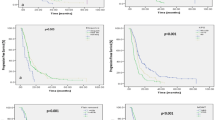

The computed ROC yielded an AUROC of 0.788 (95% confidence interval [CI] 0.686–0.873). The optimal threshold of differentiation was 2.925. At this threshold, 37 of 70 (53%) examinations had FLAIR SI in the tumor resection cavity greater than 2.925. Of these, 26 were from the ePD group and 11 were from the PsP group. The remaining 33 (47%) examinations were below the threshold. Of these, 7 were from the ePD group and 26 from the PsP group. (See Figs. 3 and 4). The corresponding sensitivity and specificity at the optimal cutoff were 0.818 and 0.694, respectively. See Fig. 5.

Subgroup analysis of biopsy-confirmed cases of PsP yielded an AUROC of 0.856 (95% CI 0.769–0.932), a sensitivity of 0.667, and a specificity of 0.957 at an optimal threshold of 4.147. When inclusion was restricted to clinically confirmed cases of PsP, subgroup analysis resulted in an AUROC of 0.667 (95% CI 0.490–0.819), a sensitivity of 0.788, and a specificity of 0.615 at an optimal threshold of 2.805. Results are summarized in Table 1.

We found lower accuracy of the increased FLAIR SI sign for differentiating ePD and PsP in glioblastoma patients treated with the Stupp than previously described. In our study group, this sign achieved a sensitivity of 82% and a specificity of 69% for detecting ePD. These results demonstrate that FLAIR SI within resection cavities may be increased in both ePD and PsP. In those patients with biopsy-proven diagnoses, the specificity of this sign was much higher, but we caution that this is a smaller population with few cases of PsP to evaluate specificity. The long-term follow-up of PsP subjects who did not undergo biopsy allows us to reasonably presume there probably was no recurrent tumor, even when the FLAIR SI in the resection cavity was increased. Therefore, our results suggest that the high specificity reported in the past is lost when patients are treated with the Stupp protocol.